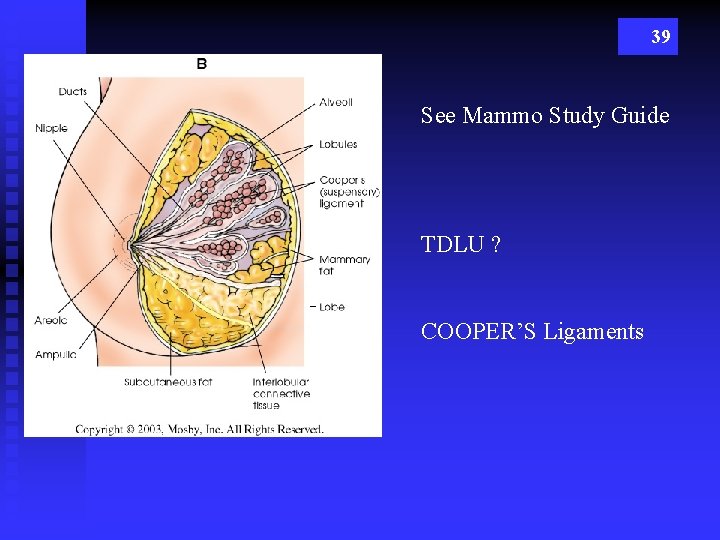

39 See Mammo Study Guide TDLU ? COOPER’S Ligaments

40 n n n Breast profile: A ducts B lobules C dilated section of duct to hold milk D nipple E fat F pectoralis major muscle G chest wall/rib cage Enlargement: A normal duct cells B basement membrane C lumen (center of duct)

TYPES OF BREAST TISSUE GLANDULAR n DUCTS n LOBES n LOBULES n TDLU n MOSTLY SEEN UPPER OUTER QUADRANT 46 STROMAL n FATTY TISSUE n CONNECTIVE TISSUE n (COOPER’S LIGAMENTS – SUSPENSATORY LIGAMENTS